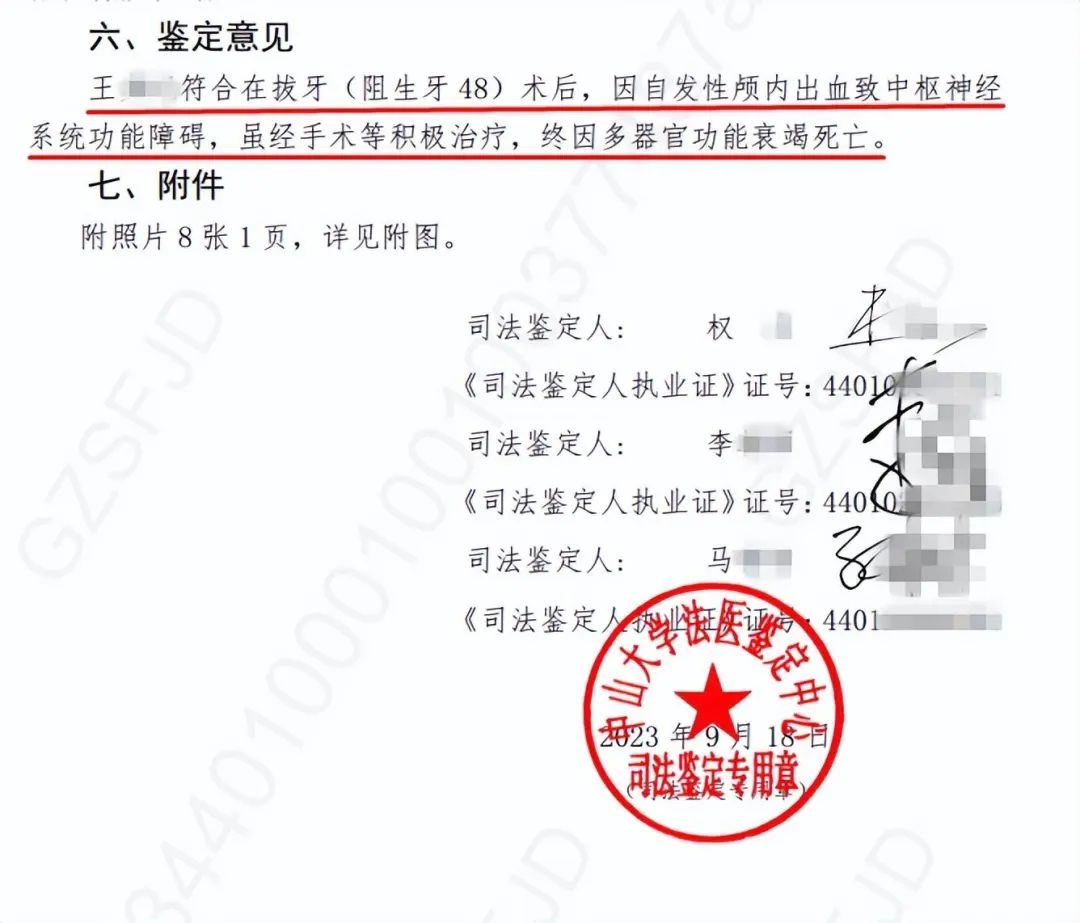

尸检报告:

系自发性颅内出血

致多器官衰竭死亡

据了解,2023年8月1日,医院和患者家属共同委托深圳市谐和医患关系协调中心人民调解委员会(以下简称“医调委”)开展医疗纠纷人民调解,后由医调委委托中山大学法医鉴定中心对患者死亡原因进行鉴定。

记者联系了医调委,相关负责人表示,中山大学法医鉴定中心在2023年9月18日出具的《中山大学法医鉴定中心司法鉴定意见书》显示:

“王某某除医源性损伤外,其余体表及内部器官未发现机械性损伤征象”;

“王某某符合在拔牙(阻生牙48)术后,因自发性颅内出血致中枢神经系统功能障碍,虽经手术等积极治疗,终因多器官功能衰竭死亡”。